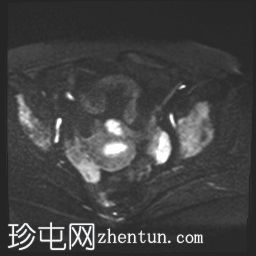

DWI

轴位

ADC

可见膀胱左侧壁有一边界清晰的T2低信号实

性病

灶,无扩散受限,均匀强化。未见膀胱周围侵犯或肾积水。

子宫底部前壁可见一小肌瘤。双侧卵巢可见无强化囊肿。盆腔及腹股沟未见异常淋巴结肿大。

这是一例经组织学证实的膀胱平滑肌瘤病例。